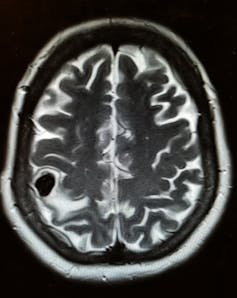

Tapeworm larvae can infect muscle and soft tissue. Brain tissue can provide a home for larvae because it is soft and easy to get to via blood vessels. Brain infection can cause headaches, dizziness, seizures, cognitive impairment and even dementia, due to an increase in cerebral spinal fluid pressure.